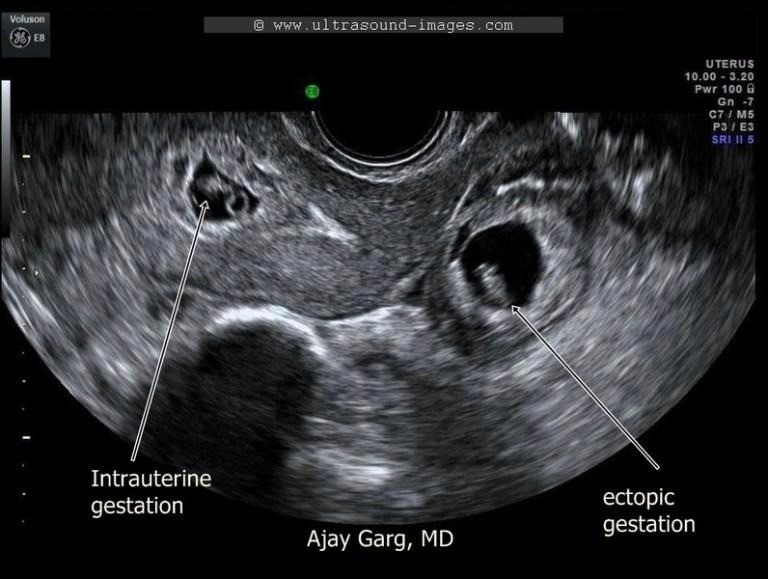

4️⃣ การตั้งครรภ์นอกมดลูก

เป็นภาวะอันตรายที่สุด!

อาการที่ต้องระวังคือ

ปวดท้องข้างเดียว

เวียนศีรษะ หน้ามืด

เลือดออกผิดปกติ

ต้องได้รับการวินิจฉัยและรักษาโดยเร็วที่สุด

อัลตราซาวด์ดูตำแหน่งการตั้งครรภ์และรก